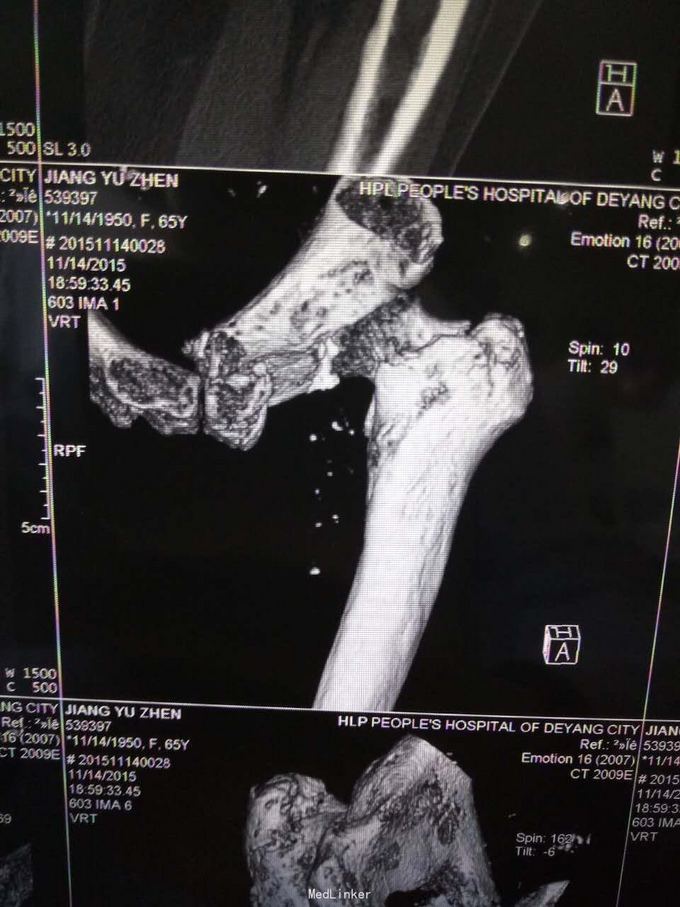

主诉:摔伤致左髋部疼痛及活动受限1小时; 病史:1小时前患者不慎摔伤,致左款疼痛,活动受限。无开放性伤口。患者半年前于华西诊断重度骨质疏松症,长期注射鲑降钙素,密固达一次。

查体,左下肢外旋畸形,髋部压痛,轴向叩击痛。 x片提示:左股骨颈、转子间骨折,左股骨耻骨上支,耻骨联合、下肢粉碎性骨折。

诊断:左股骨颈、转子间粉碎性骨折,左耻骨上支、耻骨联合、下支粉碎性骨折,重度骨质疏松症, 处理:患肢制动,牵引,注射鲑降钙素,科室讨论意见为行髋关节置换术,与换方沟通后,换方表示拒绝手术治疗,主动出院。